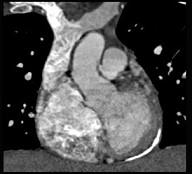

问题 男性45岁,心悸气促乏力,下肢肿胀半年余,曾患肺结核,胸部CT扫描如图所示,请选择正确的选项为 ( )

选项 A、X线、CT为常用检查方法 B、MRI显示增厚的心包较X线、CT优越,但是对心包钙化不敏感 C、心包钙化显著时也可称之为“盔甲心” D、心包钙化多见于结核 E、考虑为缩窄性心包炎 一、多项选择题

答案 ABCDE